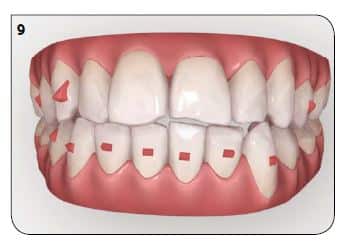

Pour cette partie du traitement : plus de stripping, moins de taquets (mais plus répartis sur les dents du bas pour le mouvement d’ingresion) et une série de 7 aligneurs supplémentaires (Fig.9 et 10).